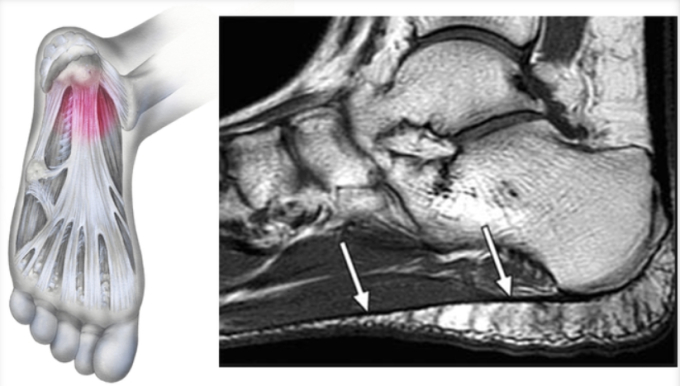

족저근막은 우리의 걸음걸이와 관련이 깊다. 발꿈치뼈(종골)와 발가락뼈를 이어주는 부채꼴 모양의 막을 족저근막이라고 부르는데 이 막이 우리 발바닥에 아치를 만들면서 충격을 흡수한다. 일종의 '쿠션' 역할을 하는 부위다. 그러나 우리의 체중을 지지하고 있는 만큼 위험에 쉽게 노출된다. 오래 서있거나 자주 걷거나 달리는 것을 주 업무로 하는 경우 족저근막에 계속적인 압력이 가해지면 미세한 상처가 된다. 이 상처는 족저근막염으로 발전하는 경우가 많다.